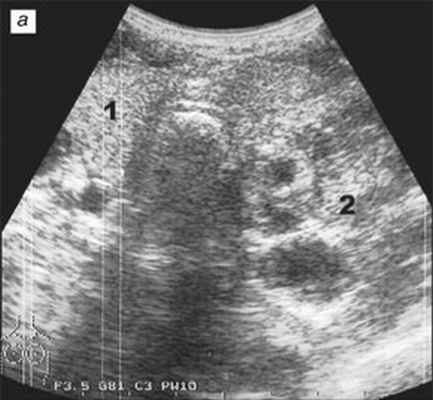

Всем больным в процессе комплексного обследования выполнено УЗИ щитовидной железы и областей регионарного лимфооттока (надключичных областей и на всем протяжении шеи) по стандартной методике, а также чрескожное УЗИ средостения по модифицированной нами методике, разработанной К. Werneke. УЗИ средостения с целью первичной дифференциальной и уточняющей диагностики проводили после клинического обследования независимо от данных рентгенологического исследования, РКТ, МРТ и других инструментальных методов.

Исследование щитовидной железы, областей регионарного лимфооттока и средостения выполняли при положении больного на спине с запрокинутой назад головой. При необходимости под плечи больного подкладывали небольшой валик. Это позволяло больным даже с короткой шеей запрокинуть голову достаточно далеко, чтобы выполнить полноценное исследование. После окончания осмотра щитовидной железы и областей регионарного лимфооттока по стандартной методике высокочастотным линейным датчиком (7-10 МГц) переходили к осмотру средостения. Для УЗИ средостения использовали конвексные датчики с частотой 3-5 МГц и с малым радиусом. Осмотр средостения проводили из яремного доступа и надключичных доступов (рис. 1, 2). Качательными движениями датчика выполняли поперечные, сагиттальные и косые эхотомограммы (ультразвуковой луч направляли кзади и каудально). Анатомическими ориентирами служили крупные сосуды средостения (дуга аорты, плечеголовной ствол, правая и левая сонные артерии, правая и левая подключичные артерии, правая и левая плечеголовные вены, верхняя полая вена), а также трахея. УЗИ средостения из парастернальных областей производили на уровне первых четырех межреберий, выполняя эхотомографические срезы в горизонтальных, сагиттальных и косых плоскостях.

а) Поперечное сканирование: 1 - неизмененная правая доля; 2 - большой узел в левой доле.